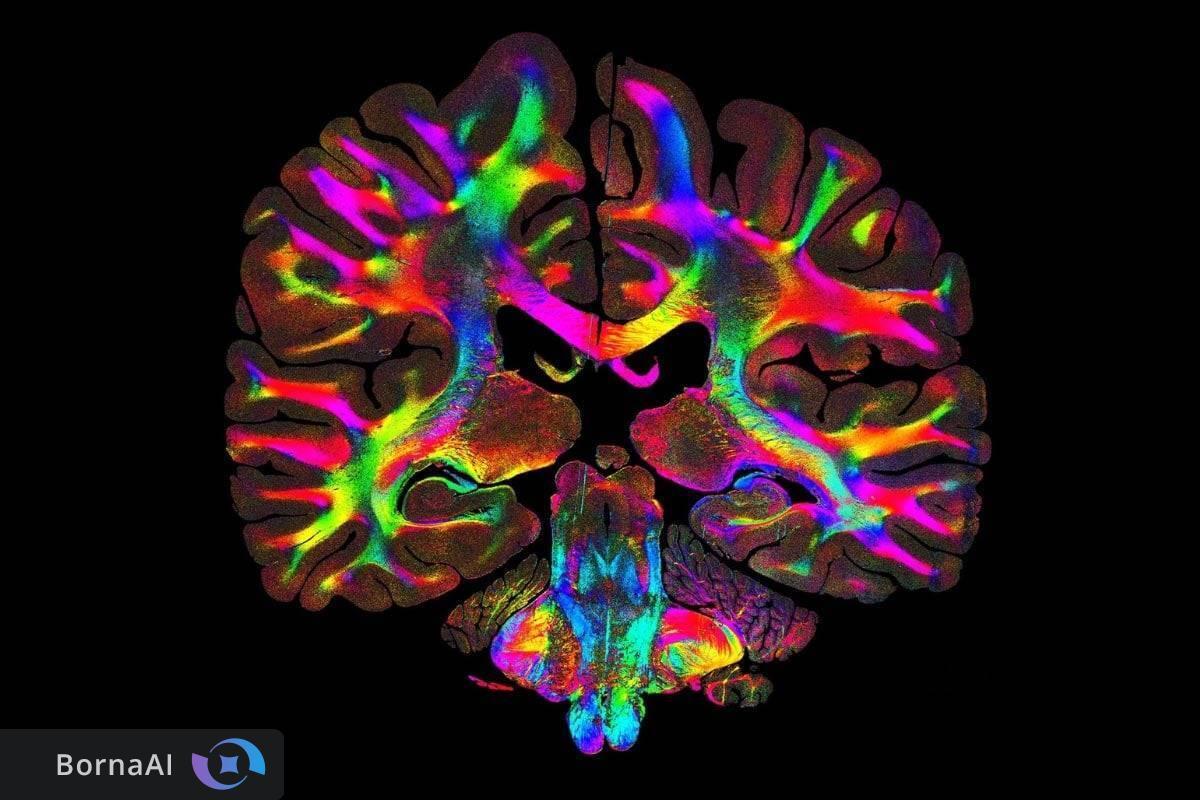

دانشمندان موفق به شناسایی شبکههای پنهان الیاف میکروسکوپی در بافتهای انسانی از جمله مغز و سایر اندامها شدهاند؛ شبکههایی که حتی در اسلایدهای بافتی مربوط به بیش از ۱۰۰ سال پیش نیز قابل مشاهده هستند. این دستاورد با استفاده از یک روش ساده مبتنی بر نور امکانپذیر شده است.

به گزارش sciencedaily، تمام اندامهای بدن انسان بر پایه شبکههایی از الیاف بسیار ظریف ساخته شدهاند که نقش اساسی در عملکرد و حفظ ساختار بافتها ایفا میکنند. در عضلات این الیاف انتقال نیروی فیزیکی را هدایت میکنند؛ در دستگاه گوارش به حرکت منظم کمک میکنند؛ و در مغز مسیرهایی را شکل میدهند که ارتباط میان نواحی مختلف تفکر و حافظه را ممکن میسازد. آسیب به این شبکههای الیافی در بروز تقریبا تمامی بیماریها نقش دارد و در اختلالات عصبی به صورت گسست ارتباط میان نورونها بروز میکند.

آشکارسازی ریزساختار مغز و اثر بیماریها

با استفاده از ComSLI پژوهشگران موفق به تصویربرداری از برشهای کامل مغز انسان شدند و جزئیات دقیقی از ساختارهای مختلف مغزی را مشاهده کردند. آنها همچنین تغییرات الیافی ناشی از بیماریهایی ماننداماس، لکوآنکفالوپاتی و آلزایمر را بررسی کردند.

در ناحیه هیپوکامپ که نقش کلیدی در حافظه دارد، بافت مغز فرد مبتلا به آلزایمر کاهش چشمگیر ارتباطات الیافی را نشان داد. مسیرهای حیاتی انتقال اطلاعات حافظه بهویژه مسیر پرفورانت تقریبا از بین رفته بودند؛ در حالی که هیپوکامپ سالم شبکهای متراکم و پیوسته از الیاف را نمایش میداد. این تصاویر امکان مشاهده مستقیم تخریب مدارهای حافظه را فراهم میکند. جالب آنکه تیم پژوهشی حتی یک نمونه مغزی مربوط به سال ۱۹۰۴ را نیز بررسی کرد و با وجود قدمت بیش از یک قرن مسیرهای پیچیده الیافی در آن قابل شناسایی بود.